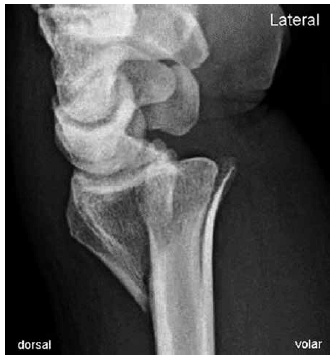

Radiografias em PA e perfil do punho de paciente masculino, 54 anos, com queda com a mão espalmada, praticando atividade esportiva.

A fratura do rádio mostrada nas imagens pode ser classificada como fratura de